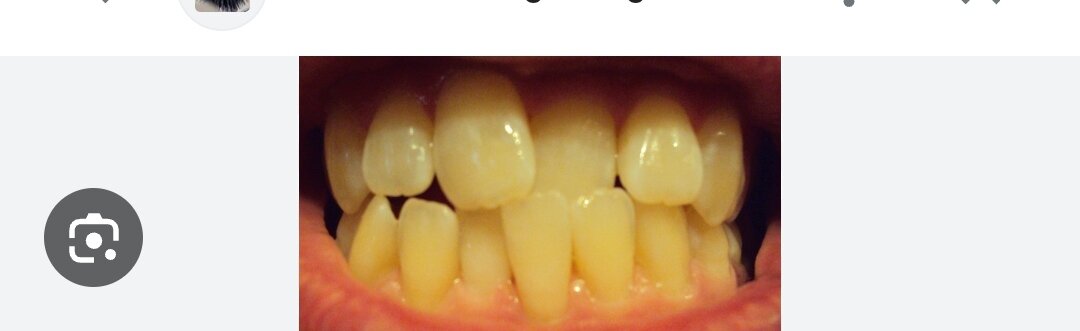

I have a deepbite, ill be having braces but my orthodontist told me its too late (and very expensive) to fix it. Altough ill be having braces, but just for 'cosmetic' effect. I have nowhere near straight teeth, especially visible in my upper front teeth. My question is, if it will be just straightening it, can it improve my jaw or side profile? Its similiar to this one i found on the internet, will pushing the right one result in forward projection?